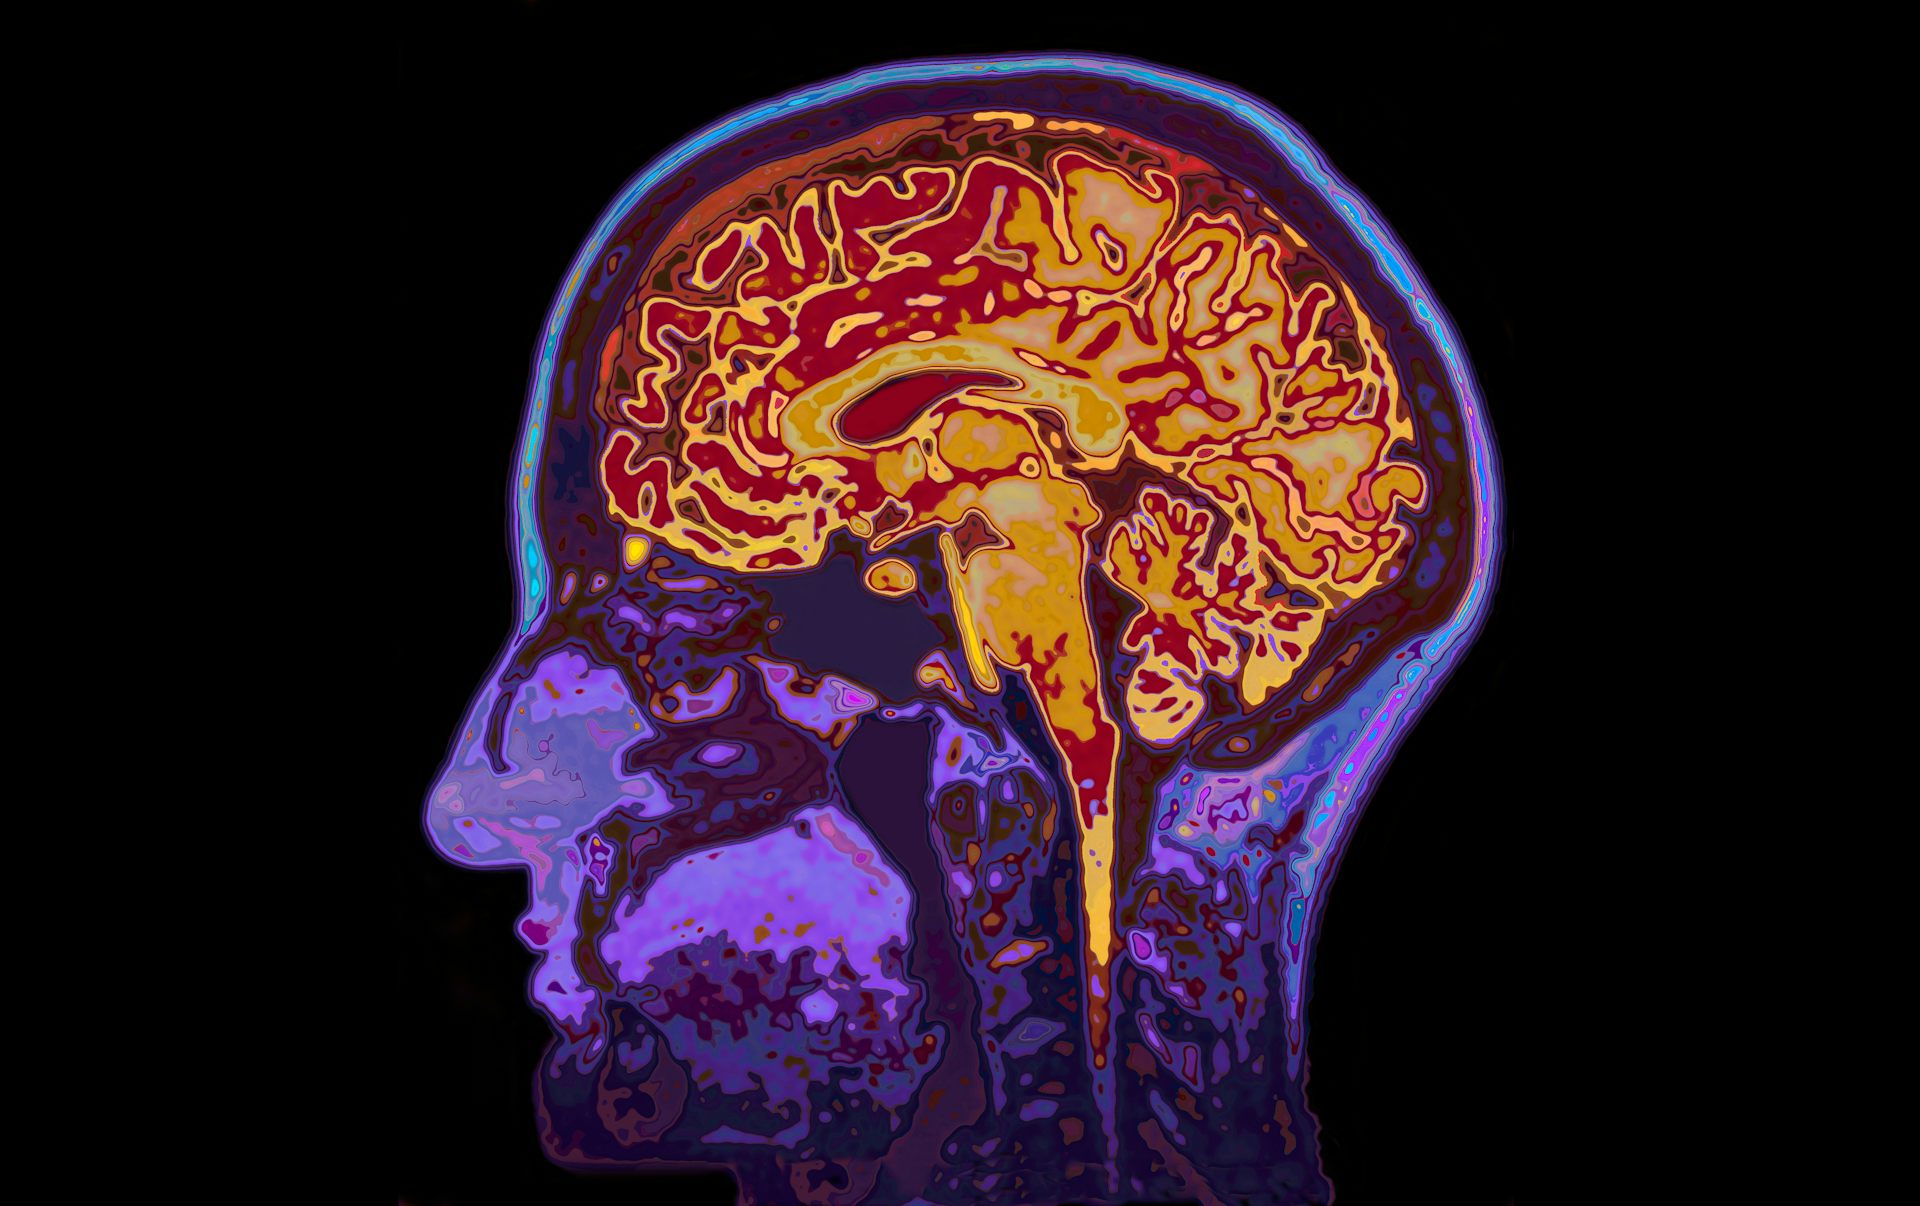

Resonancia magnética del cerebro SpeedKingz/Shutterstock